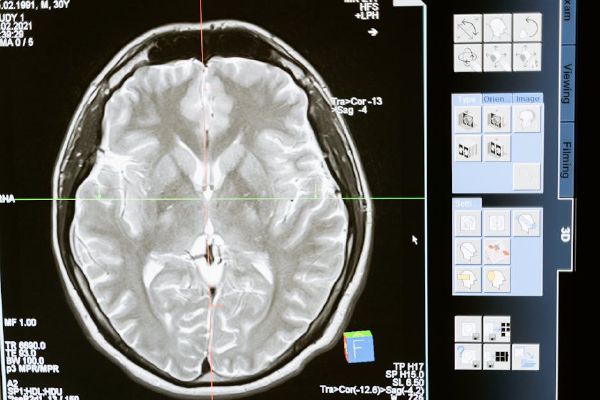

Когато тялото атакува мозъка: 5 автоимунни болести, които приличат на психични разстройства

Някои автоимунни заболявания имитират психични разстройства. Научете кои са те, как се разпознават и защо ранната диагноза е от решаващо значение.